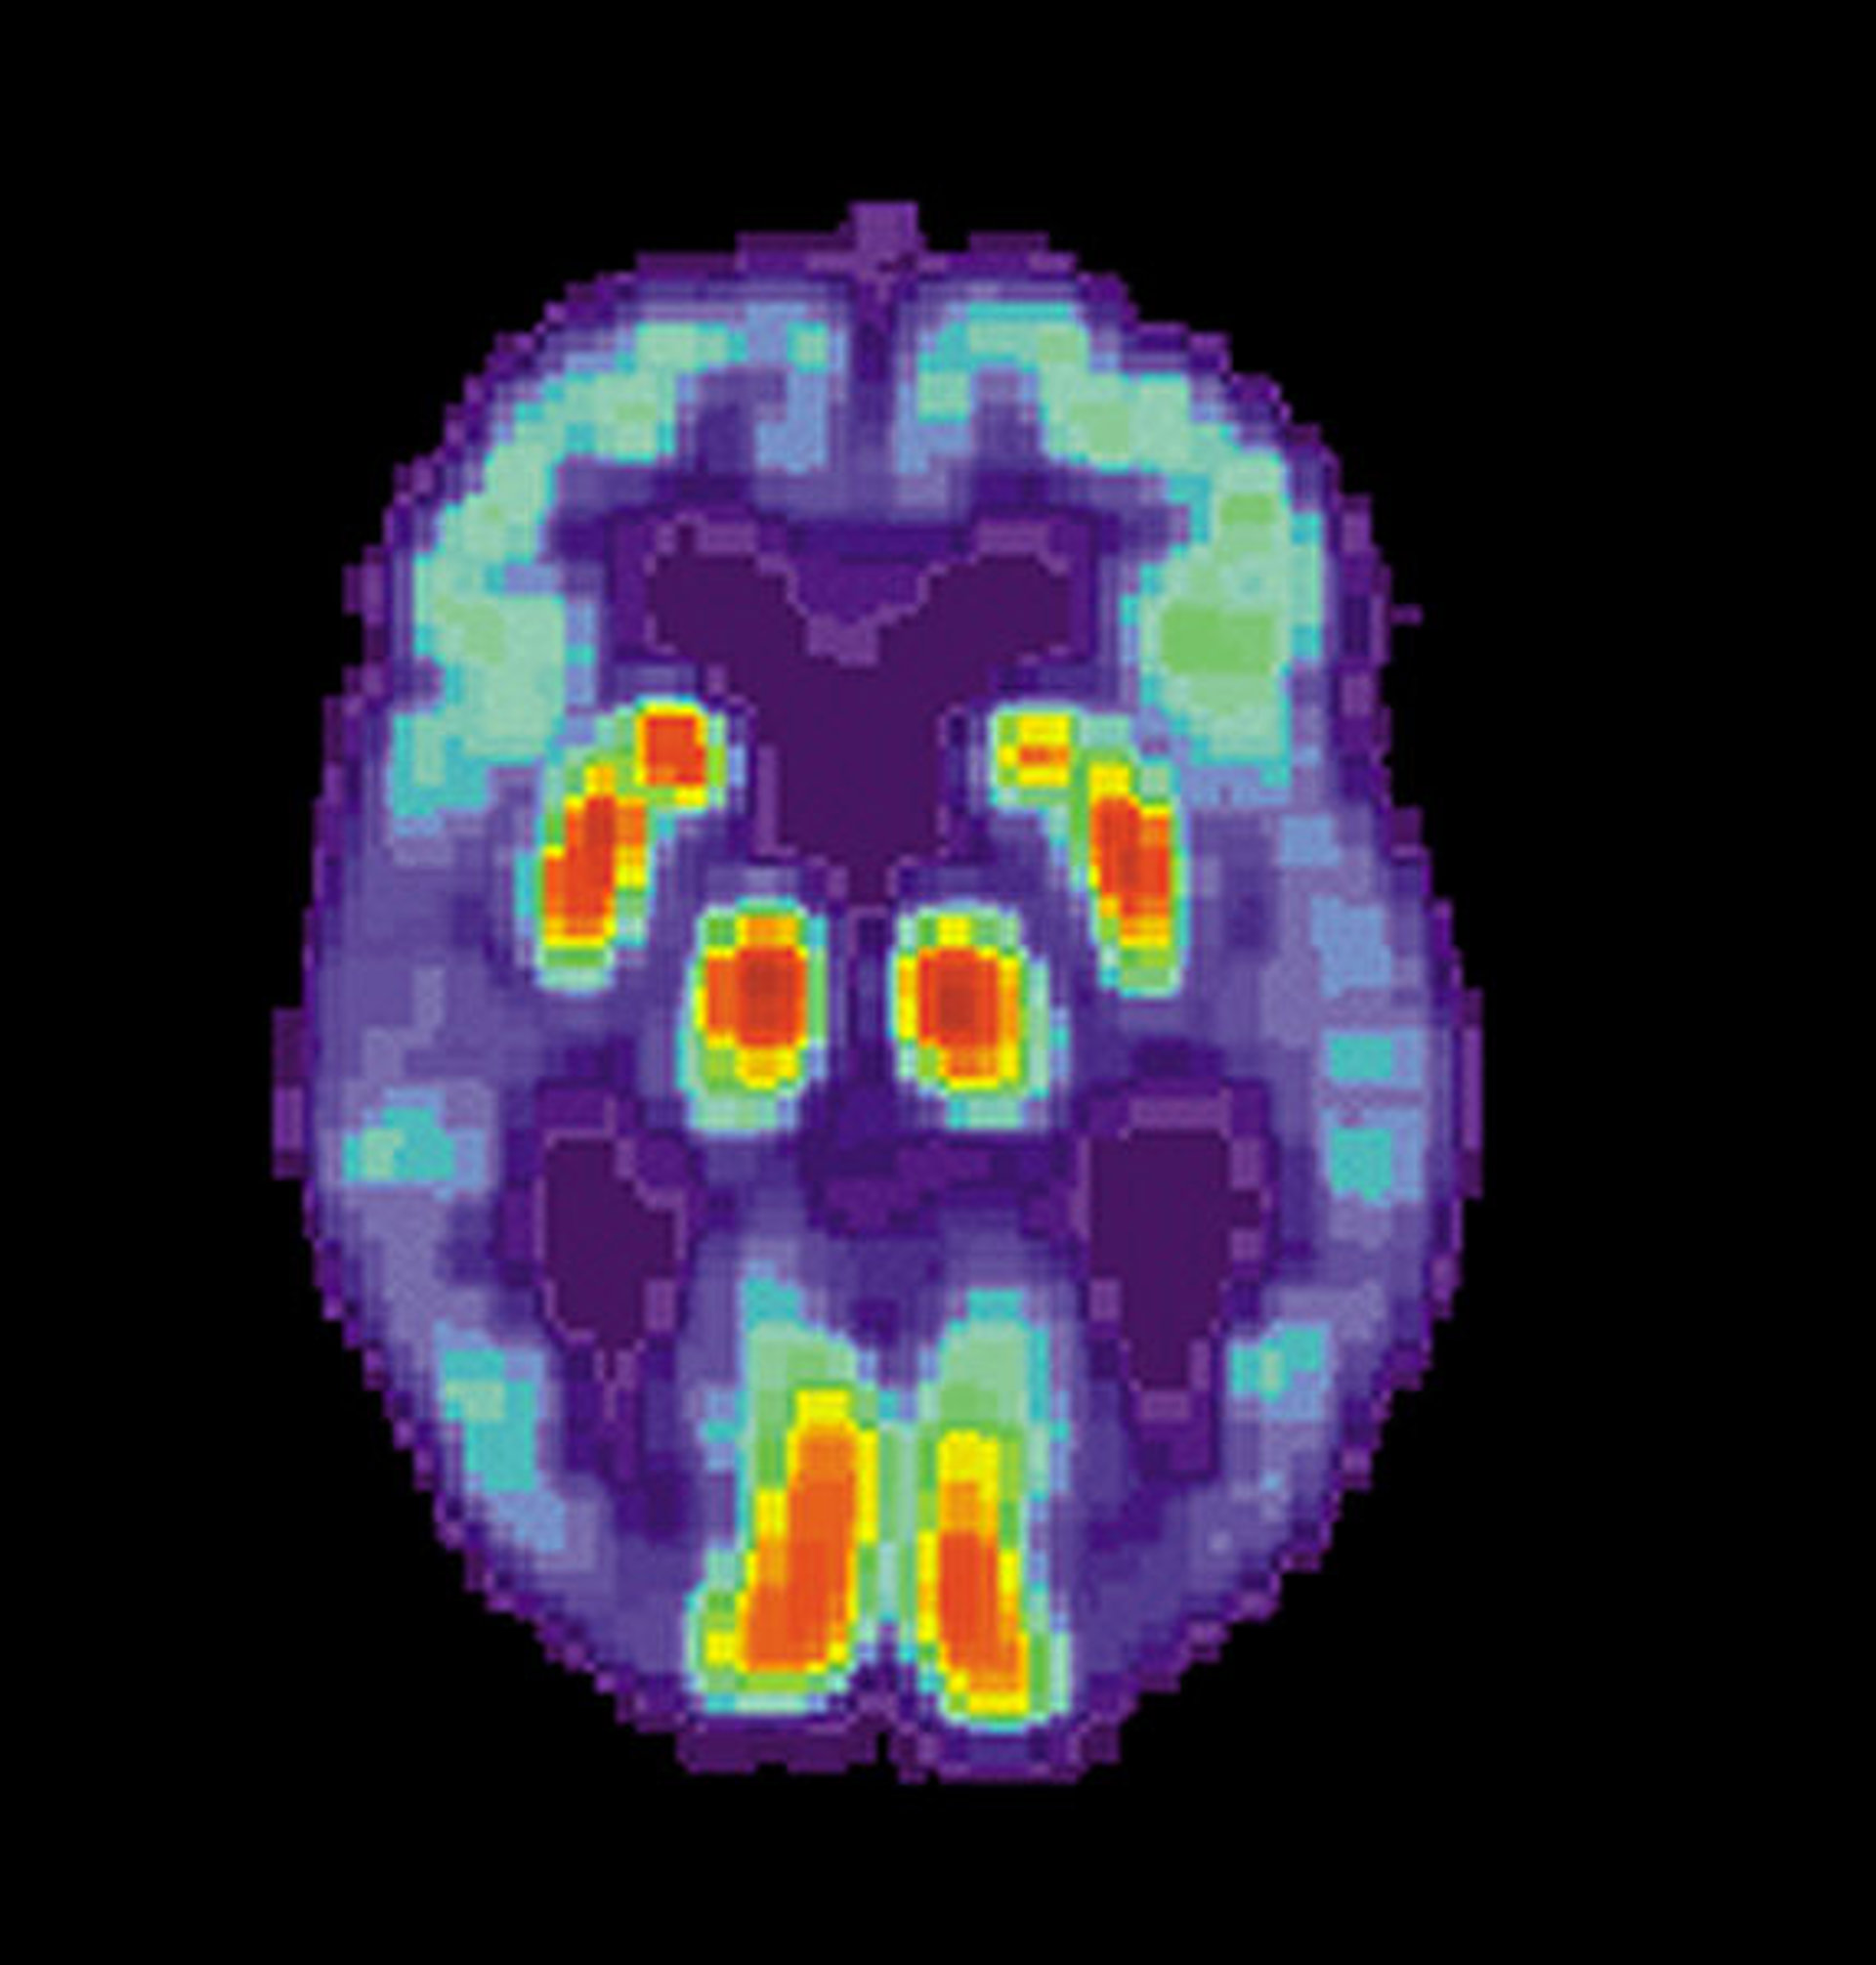

Relacionan metabolismo cerebral y Alzheimer

Investigadores de la Escuela de Medicina de la Universidad de Washington en Estados Unidos han descubierto un posible vínculo entre el metabolismo cerebral y la enfermedad de Alzheimer. Los resultados de la investigación se publican en la edición digital de la revista 'Proceedings of the National Academy of Sciences' (PNAS).

La enfermedad de Alzheimer se presenta en el cerebro en forma de depósitos ricos en proteínas, llamados placas amiloides, mucho antes de que se inicie el declive cognitivo y la demencia. Aunque la causa de la enfermedad continúa siendo desconocida, se ha descubierto que los lugares donde se acumulan las placas se solapan con un grupo de regiones cerebrales que están activas incluso cuando las personas no están participando en tareas dirigidas a objetivos.

Los científicos, dirigidos por Andrei G. Vlassenko, compararon el cerebro de adultos sanos con el de aquellas personas con enfermedad de Alzheimer para determinar si el patrón de acumulación de placas puede unirse al metabolismo cerebral subyacente.

Los resultados mostraron que en personas con Alzheimer las placas se acumulan en regiones del cerebro que se corresponden con regiones cerebrales en personas sanas en las que se eleva un proceso metabólico llamado glicólisis aeróbica.

Mientras que algunas regiones, como la corteza prefrontal y parietal, que se pensaba que tenían un papel en el autoreconocimiento y las tareas de control, mostraban niveles elevados de glicolisis aeróbica, otras como el cerebelo y la formación hipocámpica, que se creen afectan al control motor y la memoria, mostraban niveles bajos.

Dado que la glicolisis aeróbica podría ayudar al cerebro a generar elementos constitutivos de las células, manejar subproductos metabólicos tóxicos y regular la mortalidad celular programada, los descubrimientos sugieren un posible vínculo entre las funciones cerebrales a las que proporciona energía la glicólisis aeróbica y el inicio de la enfermedad de Alzheimer.